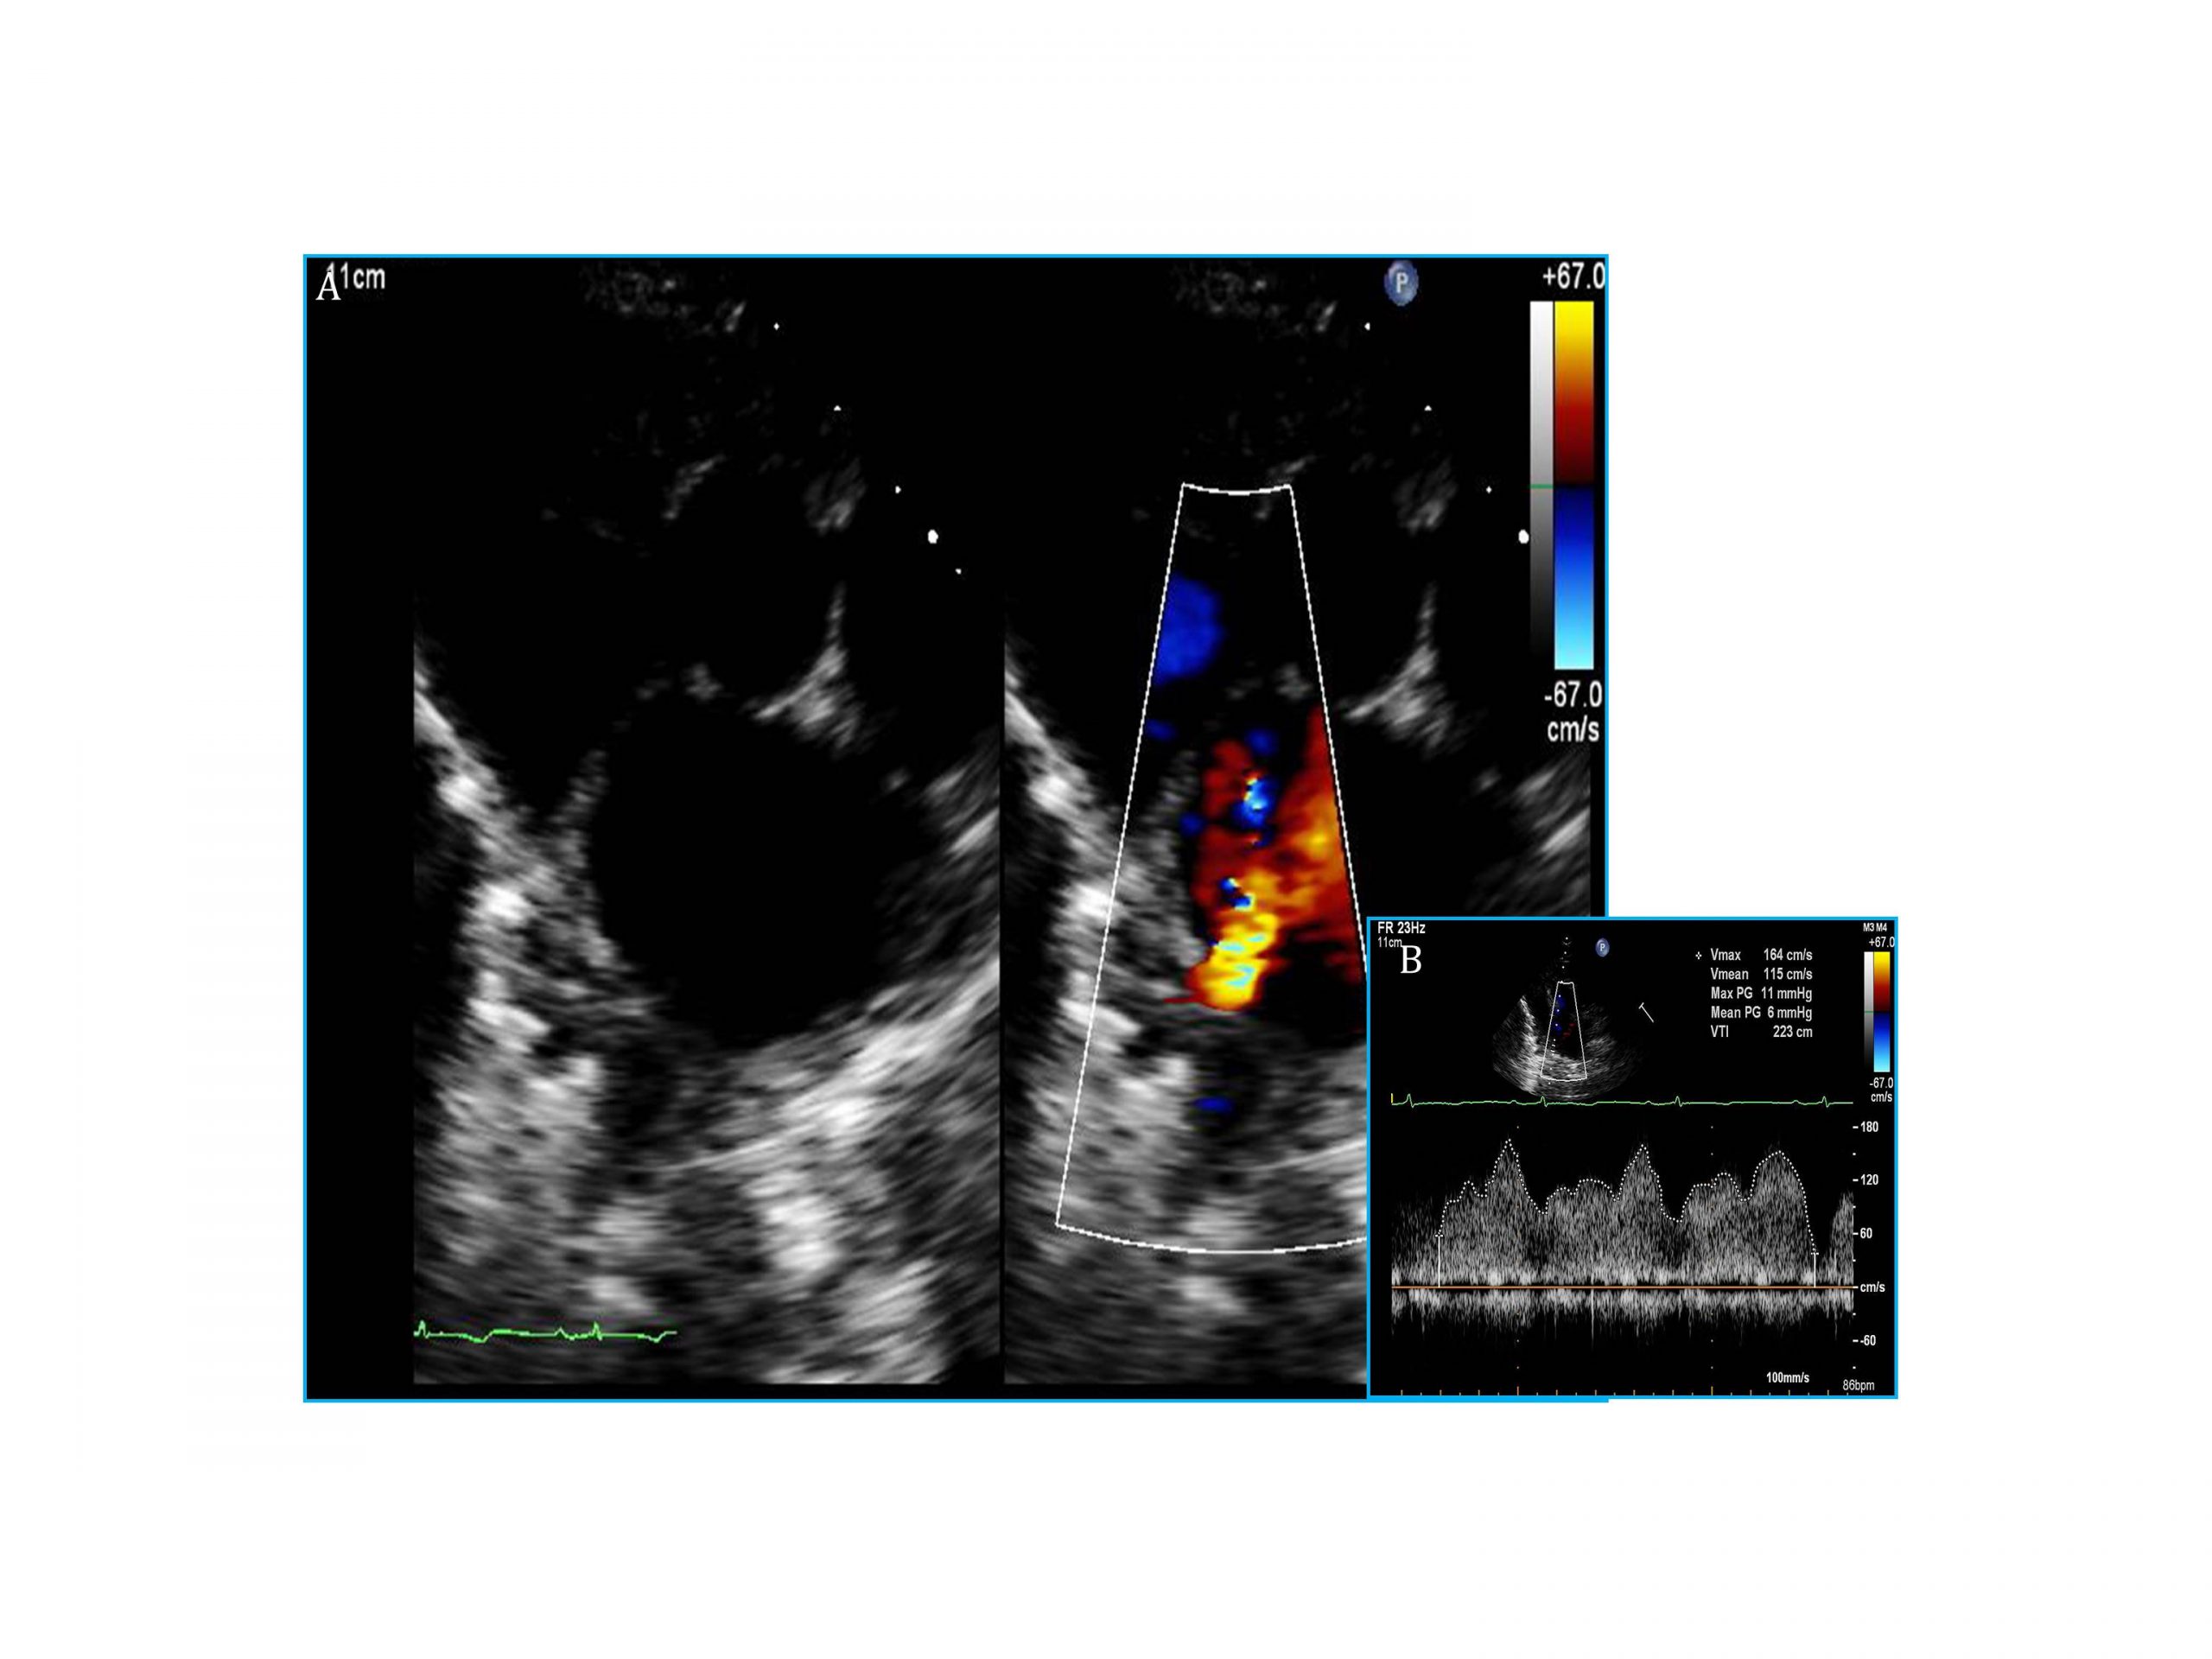

– 14 months post-operatively: transthoracic echocardiogram (TTE) 6 mmHg mean gradient (MG) across anastomosis (Figure 1)

– Hemodynamics revealed a baseline 9 mmHg MG across lesion

– Residual cath MG 3mmHg; Patient started on antiplatelet therapy

– At one month follow-up: 1mmHg MG by TTE